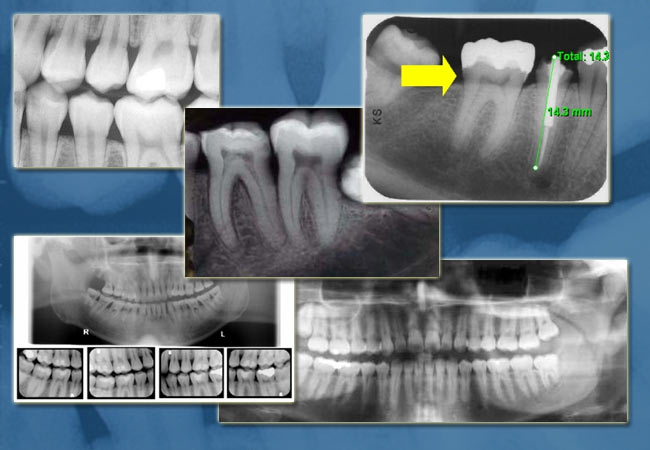

• Archival and Diagnostic Review Software for a Dental X-ray application.